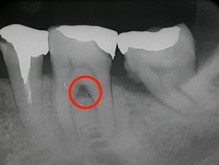

歯周病の進行度合いを調べるために、当院では「CT」を活用します。一般的なレントゲンと異なり、CTは立体的に治療部位を捉えることができるため、歯を支える顎の状態まで詳細に把握することができます。